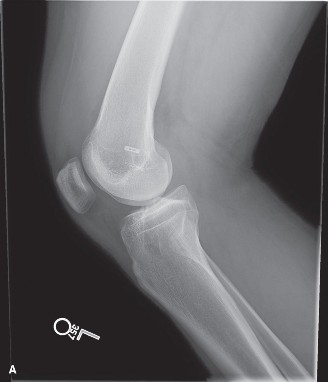

Standard radiographic evaluation of the knee is the first-line imaging modality for anterior knee pain. The patient's initial X-rays (Figures 9-1 A-C) include a weight-bearing anteroposterior (AP), a true lateral at 30 degrees of flexion, and an axial (Merchant or Sunrise) view.

The AP view demonstrates normal tibiofemoral joint spaces with no evidence of osteochondral lesions, loose bodies, or degenerative changes. The lateral view is scrutinized for patellar height. The Insall-Salvati ratio (the ratio of the patellar tendon length to the greatest diagonal length of the patella) is calculated at 1.05, which falls within the normal range (0.8 to 1.2), ruling out patella alta or baja. The lateral view also shows no evidence of trochlear dysplasia; the crossing sign is absent, and the trochlear bump is not prominent.

The Merchant view is arguably the most critical radiograph for this patient. It reveals a subtle lateral tilt of the patella and mild lateral subluxation. The sulcus angle measures 138 degrees (normal is typically <145 degrees), indicating adequate trochlear depth. However, the congruence angle is slightly lateralized, confirming the clinical suspicion of lateral patellar maltracking. There is no evidence of advanced patellofemoral osteoarthritis, osteophyte formation, or subchondral sclerosis.